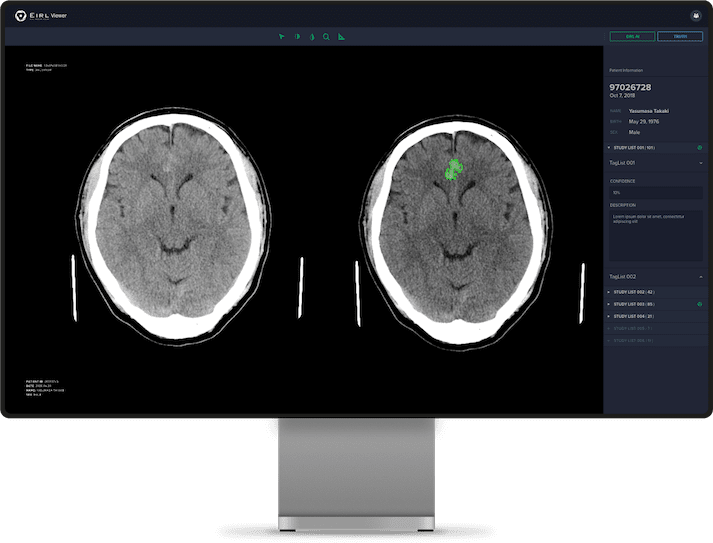

頭部CT画像から

頭蓋内の高吸収領域を自動抽出

頭部単純CTの画像情報から、頭蓋内の高吸収領域を抽出し強調表示をおこないます。各スライスの高吸収領域が色付けされて表示されます。